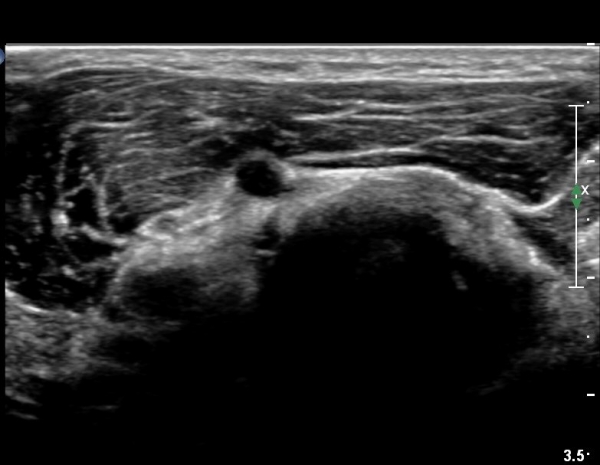

ŽÃÊÀÚ¸¦ ȸ¿Ü±Ù ºÎÀ§±îÁö À̵¿ÇÏ´Ï ³¶Á¾Àº °í³ªÂûµÇÁö ¾Ê°í µÎ ȸ¿Ü±Ù »çÀÌ¿¡ Àִ  Èİñ°£½Å°æ

ºÎÁ¾ÀÌ °üÂûµÈ´Ù(»çÁø 4).

Èİñ°£½Å°æ Á¾´Ü¸é°Ë»ç¿¡¼­ ³¶Á¾°ú ÀÎÁ¢ÇÏ¿©  À§Ä¡ÇÑ Èİñ°£½Å°æÀÇ ºÎÁ¾ÀÌ °üÂûµÈ´Ù(»çÁø 5, 6).